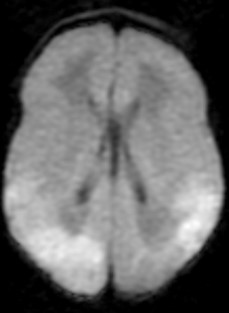

Segunda gestación gemelar de una madre sana de 40 años. Parto mediante cesárea electiva por cesárea previa a las 38 semanas de gestación. Nace segundo gemelo con prueba de Apgar 9/10/10; pHau:7.25. Peso de nacimiento: 3215g (p63), longitud: 49,5cm (p70) y perímetro cefálico: 34cm (p67). A las 60 horas de vida presenta empeoramiento clínico con alteración del estado de conciencia progresivo con mala coloración cutánea y alargamiento del tiempo de recapilarización. Presenta hipoglucemias mantenidas e inicia un estado epiléptico refractario al tratamiento con un pico febril al 7º día de vida. Se realiza RM cerebral ( Figura 1A, 1B) a las 39 semanas de EPM.

En la Figura 1A, se aprecia una pérdida de diferenciación entre córtex y substancia blanca, compatible con edema cerebral difuso, y en la Figura 1B se aprecia una disminución de la difusividad a nivel del córtex occipital derecho y parietal bilateral. Además nuestro paciente presentó hipoglucemias mantenidas los primeros días de vida que podrían explicar la lesión occipito- parietal hallada en la RM. Nuestro paciente fue exitus a los 9 días de vida por una enterocolitis fulminante.

Figura 1B. RM cerebral . Corte axial-DWI.